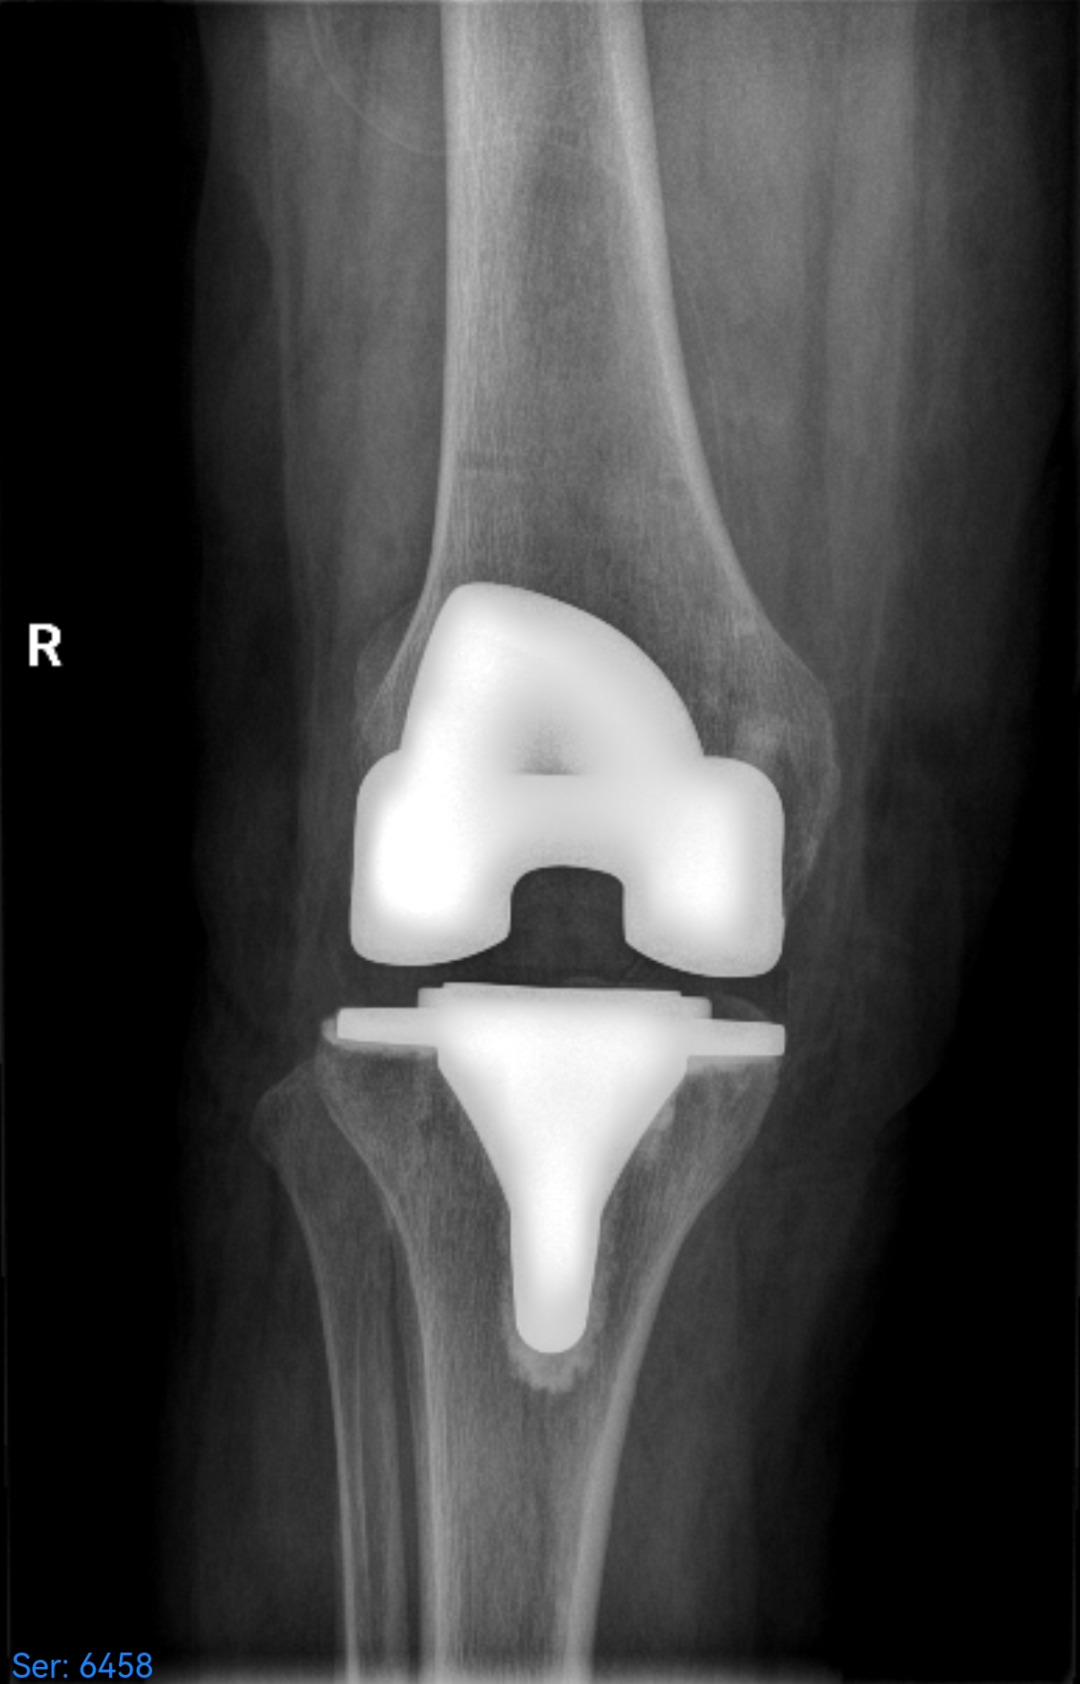

术后

术后第一天,患者在骨三科医护人员的指导下便能下床行走,肢体活动度良好,原有疼痛症状消失。患者及家属对此结果十分满意。在后续的住院期间,骨三科医护团队为患者制定了个性化的康复方案,最终助力患者顺利出院。

手术过程中,骨三科团队通过操控机械臂实施截骨,操作精度达到毫米级,使得膝关节假体被精准安放在理想位置,由此患者术后下肢力线得以完美恢复。与此同时,这种高精度操作大幅减少了对软组织的松解干扰,不仅显著减轻了患者的疼痛感,还有效降低了术中出血量。